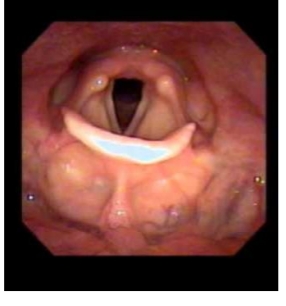

Intermezzo: directe laryngofaryngoscopie

larynx

Supraglottis (epiglottis, ary-epiglottische plooi, valse stemband

Glottis

Subglottis

Supraglottis

Supraglottis: snelle

metastasering, vaak

laattijdig symptomen.

Stridor bij grotere tumoren